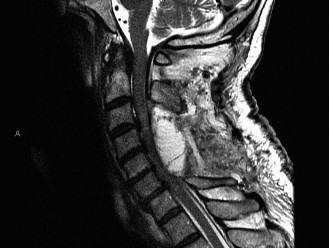

Determine optimal definitive treatment for spinopelvic dissociation? CASE 4 You are called to the emergency department to evaluate a 32-year-old man with a history of intravenous drug use who presents with a 2-week history of increasing neck pain and a 2-day history of fevers and progressive weakness in his arms and legs. On examination, he has 3/5 strength globally in his upper and lower extremities and is unable to ambulate without assistance.

The correct answer is (C). While x-rays and a CT scan may be helpful in evaluating overall alignment of the cervical spine as well as possible bony changes, an MRI would be the best imaging modality to visualize any neurologic involvement leading to the patient’s deficit. With the patient’s history, an infectious etiology is highly likely. While a bone scan can demonstrate increased activity in an area of infection, it does not help localize the exact location and extension of neurological involvement. In the event that an MRI is contraindicated, a CT scan, ideally with

intrathecal contrast, would be a reasonable alternative. Advanced imaging is shown inFigure 1–10. What is the most likely diagnosis? 1. Ossification of the posterior longitudinal ligament

Figure 1–10

The correct answer is (B). The T1 sagittal MRI demonstrates an epidural process that extends behind the C2, C3, and C4 vertebral bodies. There is destruction of the C3–4 disc space, which likely represents discitis/osteomyelitis. The epidural mass is most likely an abscess originating from the C3–4 disc space. OPLL, or ossification of the posterior longitudinal ligament, would typically be seen as an intermediate